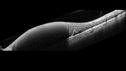

62 year old african american female with moderate chronic hypertension A few weeks ago she was at work and noticed a dark spot in the right eye. Since then it is not getting any better. She was out of town when it happened. VA OD: Dcc6’/200 Ncc20/400 VA OS: Dcc20/32 NccJ1